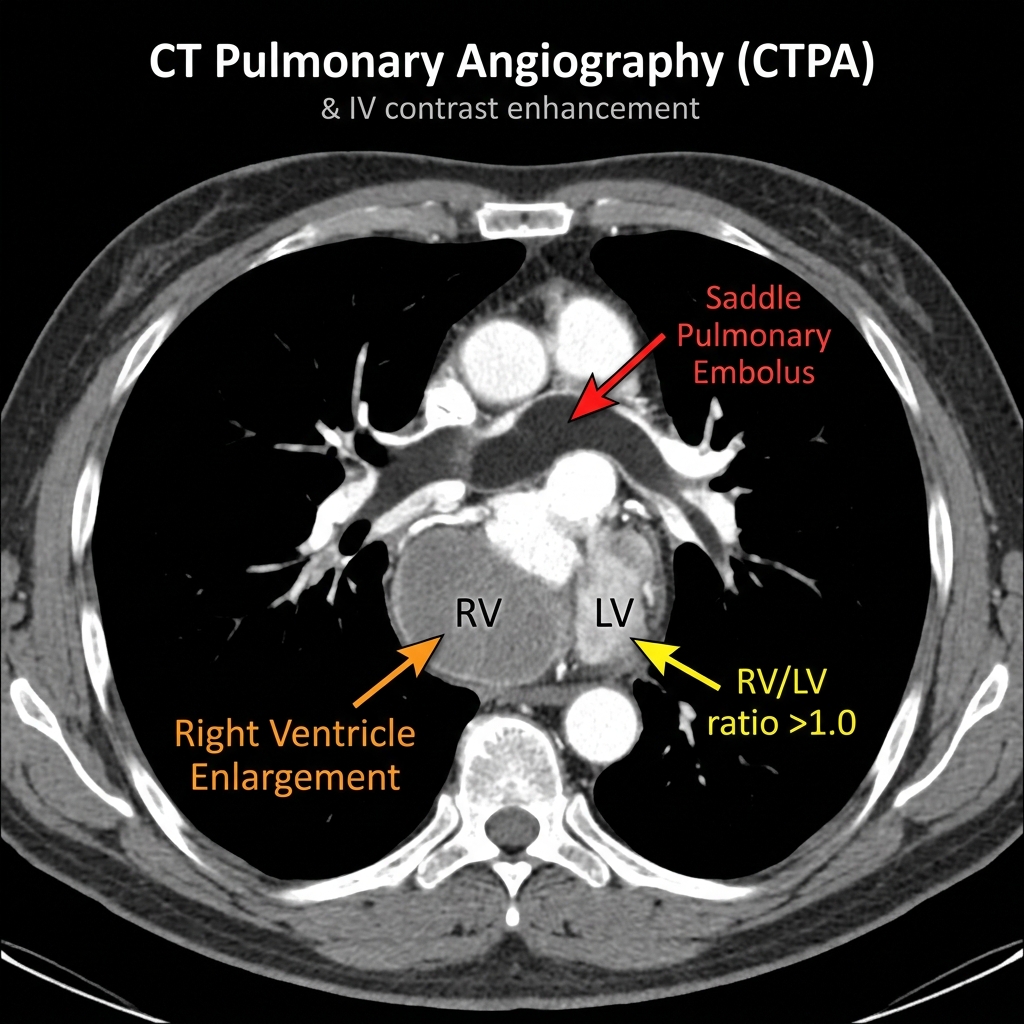

A comprehensive guide to CT Pulmonary Angiography (CTPA) for pulmonary embolism diagnosis. Covers direct and indirect CT signs, right heart strain assessment, clot burden scoring, and structured reporting.